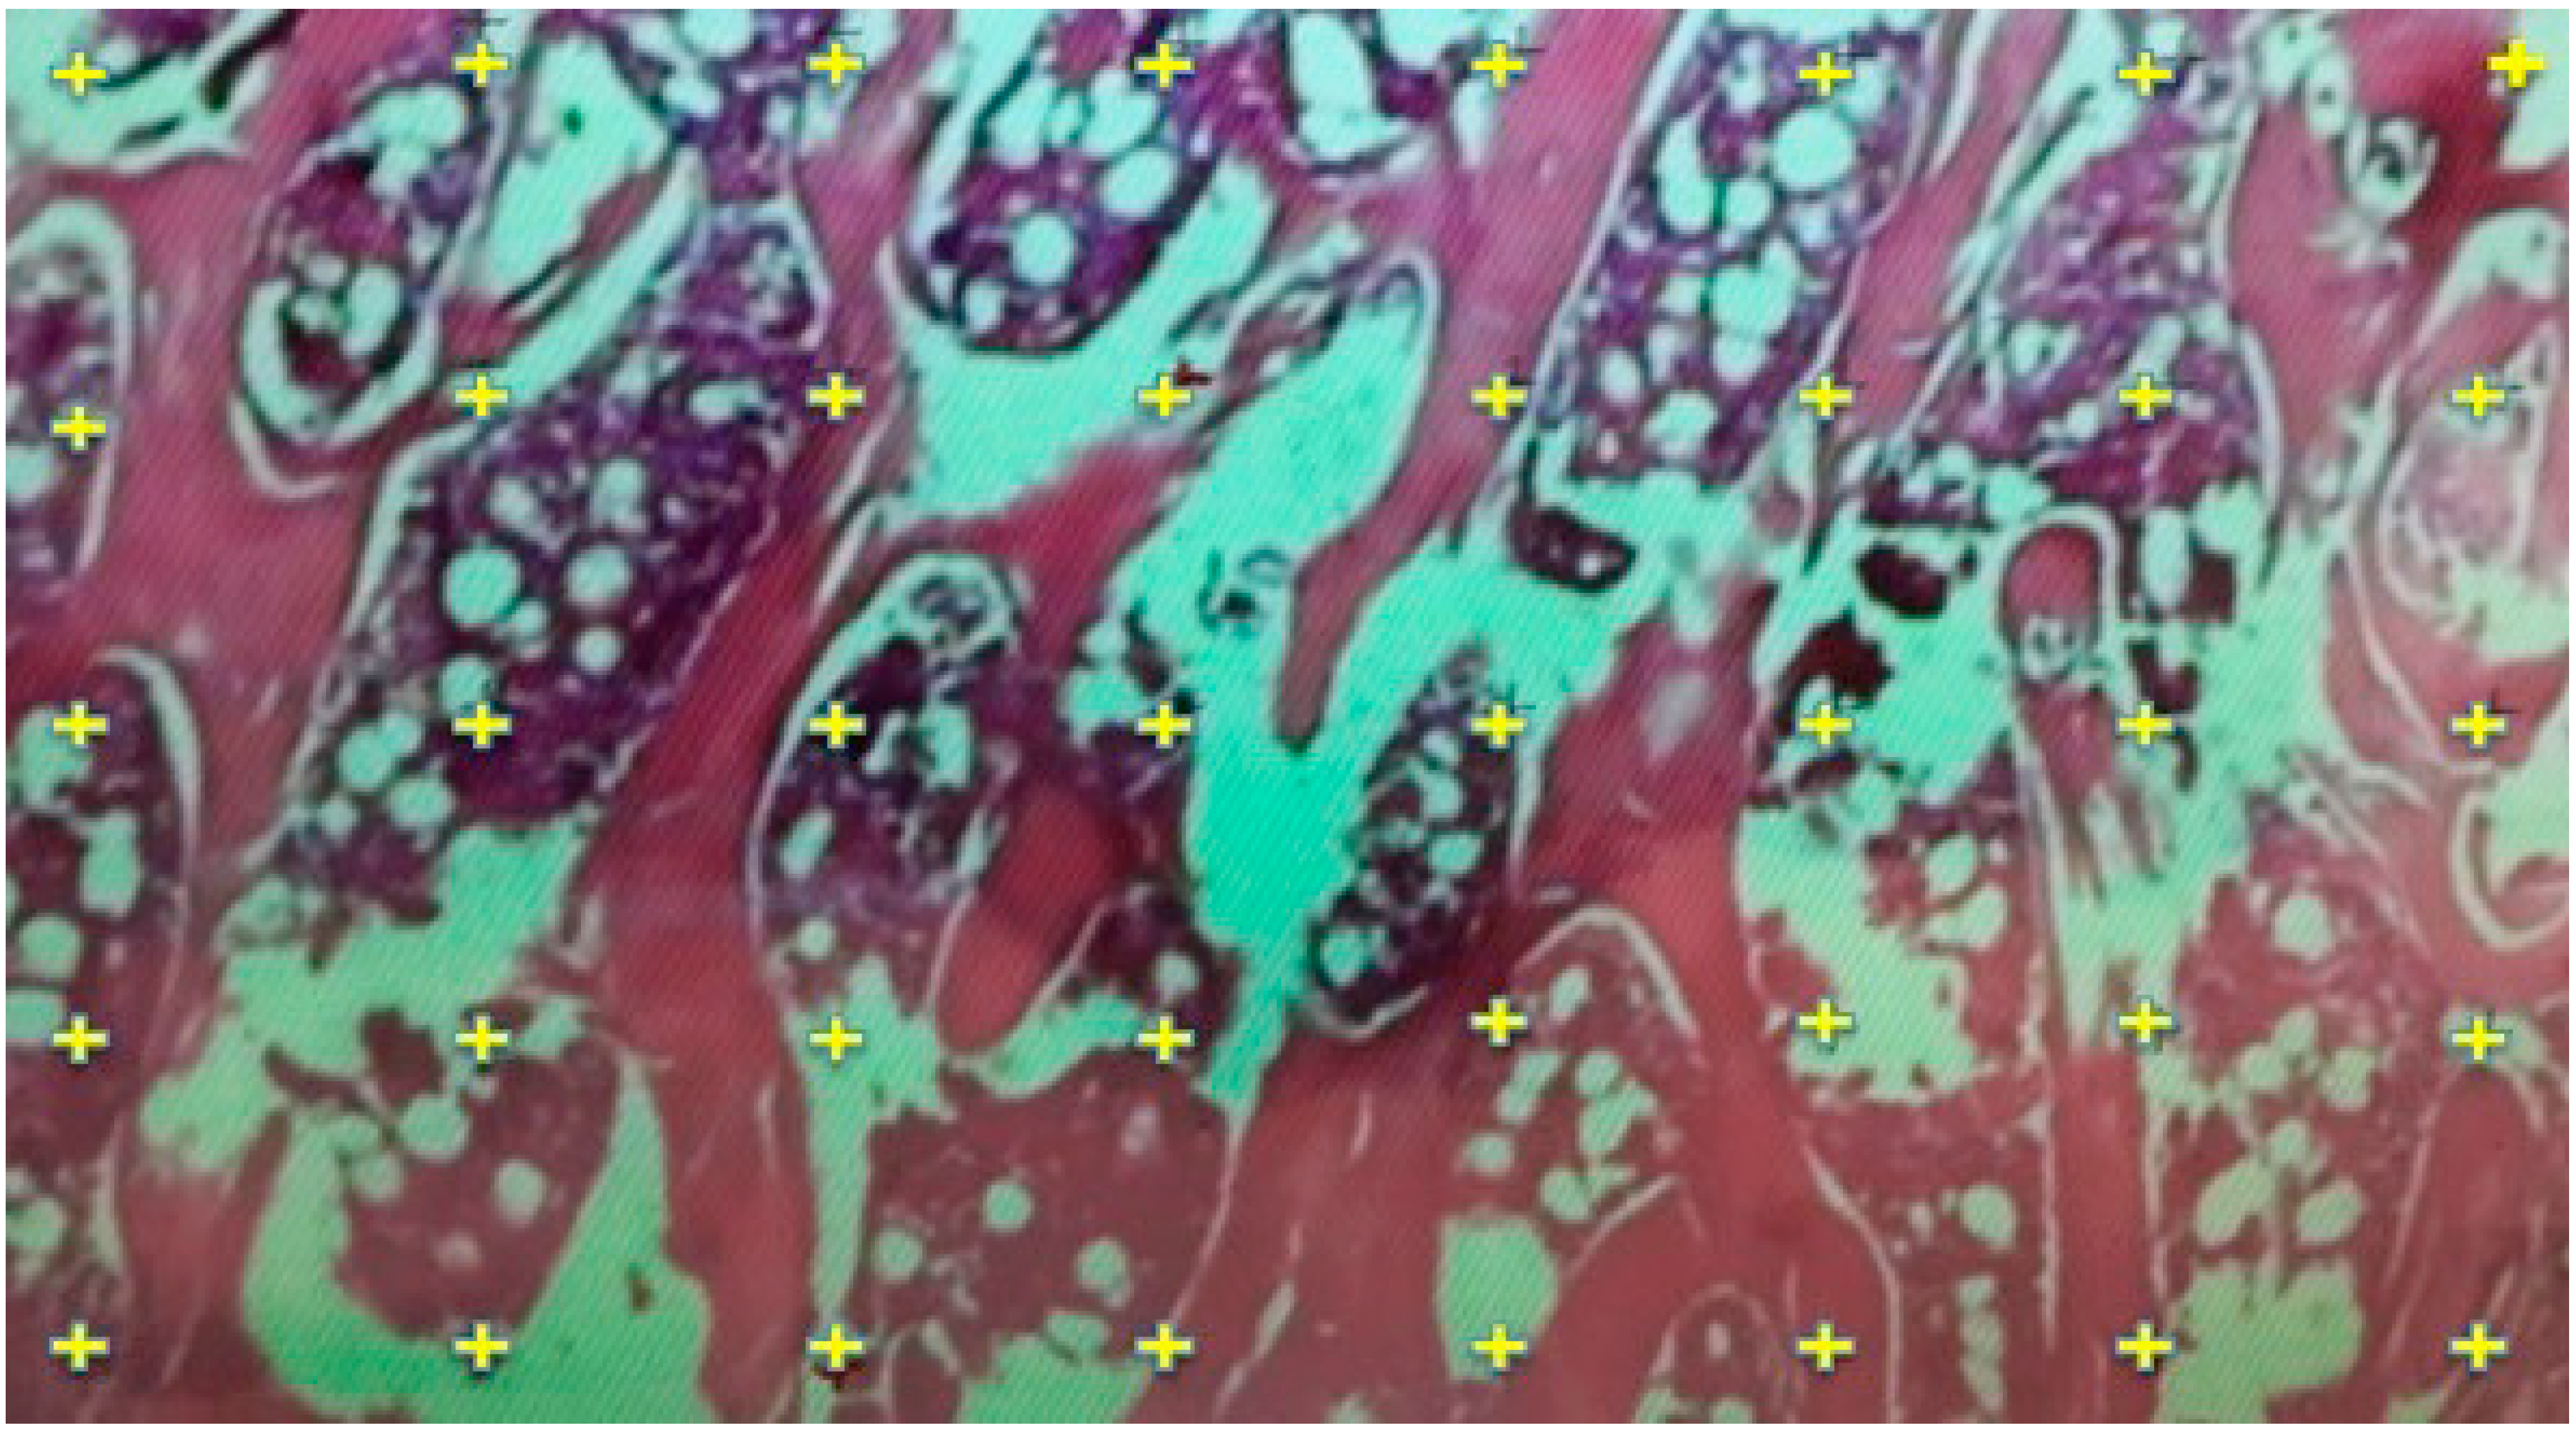

3.4. Results of Histological Evaluation

3.5. Results of Histomorphometric Evaluation for Trabecular Thickness and Trabeculae Number